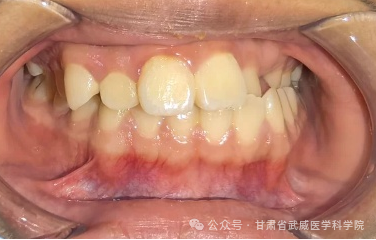

牙列不齐,医学上称为“错颌畸形”,是指儿童在生长发育过程中,由先天的遗传因素或后天的环境因素(如疾病、口腔不良习惯、替牙异常等)导致的牙齿、颌骨、颅面的畸形。

·“地包天”: 下牙包住上牙,会导致面中部凹陷,形成“月牙脸”。

·龅牙/小下巴: 上颌前突或下颌后缩,导致开唇露齿,嘴唇无法自然闭合。

·偏颌: 长期单侧咀嚼导致脸型不对称,变成“大小脸”。